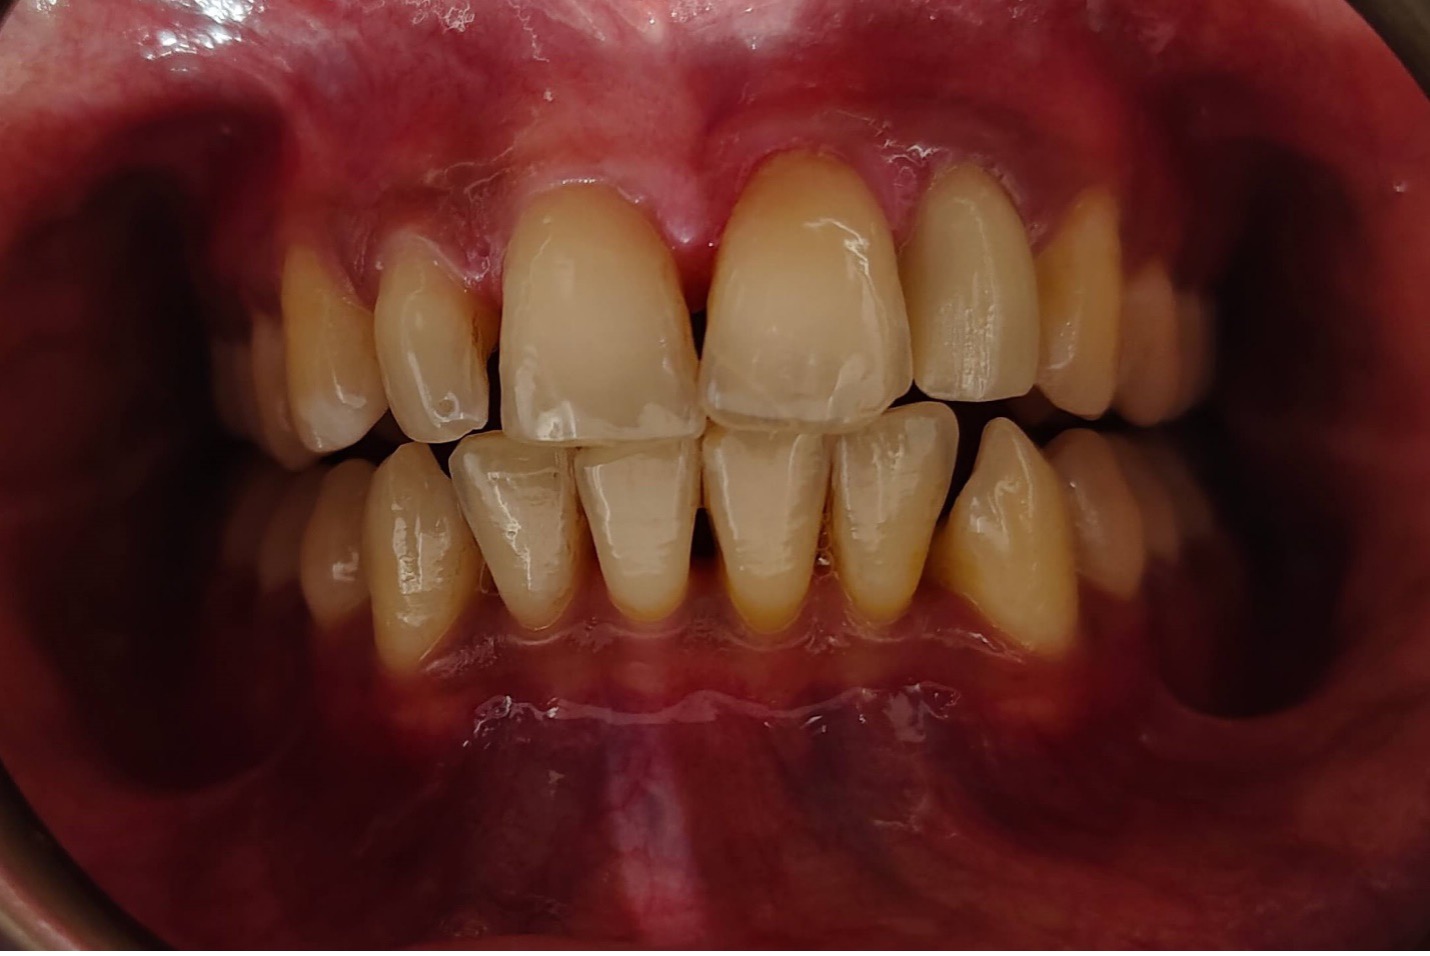

A dental crown is a tooth- shaped cap placed over a damaged or decayed tooth to restore its shape, size, and appearance. Crown is fabricated from various types of materials such as porcelain, zirconia, ceramic, metal alloys, or a combination of these materials and they are cemented over the prepared tooth. When the crowns are cemented, they encase the entire visible structure of the prepared tooth that lies at and above the gum line.

Dentists recommend a crown when a large filling needs replacing or half of the tooth is missing or malformed. Crowns are caps made to fit over an existing tooth which are often recommended following a root canal treatment to protect the remaining structure of the tooth because strength is compromised by extensive decay and infection. Alternatively, crowns are used to cosmetically treat a smile where teeth are heavily filled and the provision of a crown increases tooth stability and improves appearance.

Zirconia crowns are a type of dental crown made from zirconia, a very strong and durable ceramic material known for its aesthetic qualities. They are custom-made to fit each patient's mouth and are designed to blend in naturally with the remaining teeth for the long term. They cover the damaged or decayed teeth, providing strength, functional restoration and a natural appearance.

Zirconia crowns are popular because they can withstand biting and chewing forces well, are biocompatible (unlikely to cause allergic reactions), and can be matched closely to the color of natural teeth. They are a popular choice in modern dentistry and it makes them a preferred choice for many dental patients who are seeking long-lasting natural treated tooth protection, longevity, comfortable bite and aesthetically pleasing dental restorations.